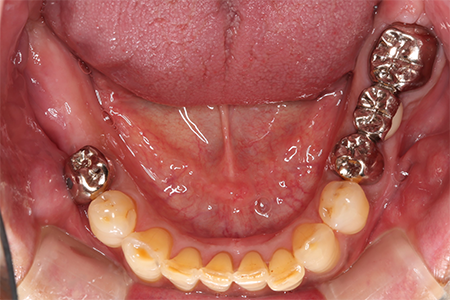

この患者様は長い事歯科医院には通っておらず、下の歯は前歯以外は全て崩壊していることが分かります。

また、奥歯がなくなってからの期間が長かったため、入れ歯が入るスペースが奥にないのが分かります。